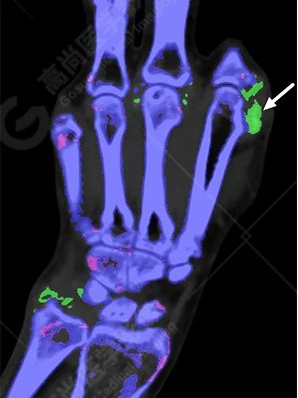

雙手VR圖像

雙能CT痛風染色圖像:

白色箭頭提示痛風石沉積。